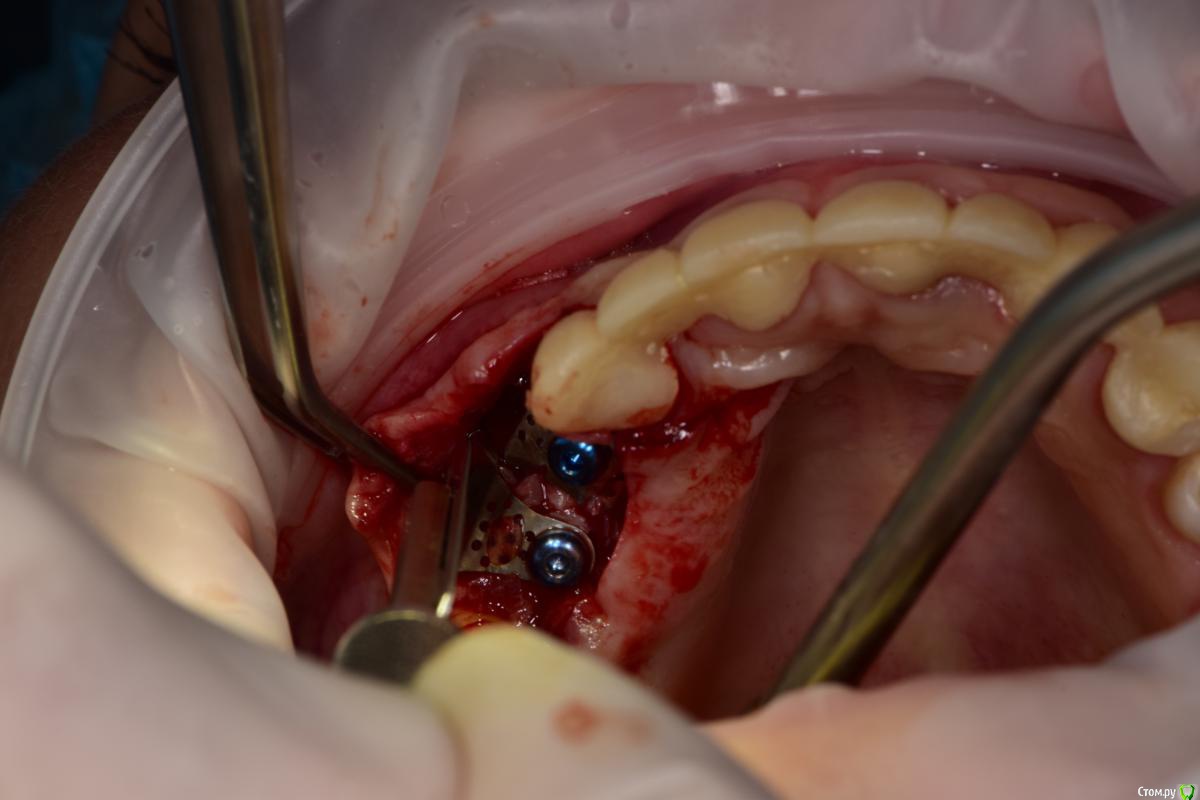

Петр Бриньковский Опубликовано 20 мая, 2017 Поделиться Опубликовано 20 мая, 2017 Южнокорейские импланты с использованием спейсеров и прикручиваемых титановых сеток при НКРзалесных ренген.bmp 4 Ссылка на комментарий

Петр Бриньковский Опубликовано 21 мая, 2017 Автор Поделиться Опубликовано 21 мая, 2017 (изменено) Чем сетки покрывали? Почему выбрали этот метод?PRF мембраны, метод работает достаточно неплохо , в последнее время очень часто так делаю после того как в Корею осенью к доктору Паку на конференцию съездил. Сетки разных форм и ширины и с помощью спейсеров можно увеличиваться немного по высоте(1-3 мм). Каркас достаточно надежный и впоследствии достаточно легко удаляются без сильного отслоения, а на сами спейсеры прикручивается дополнительно формик(можно одномоментно). Изменено 21 мая, 2017 пользователем Петр Бриньковский Ссылка на комментарий

Петр Бриньковский Опубликовано 21 мая, 2017 Автор Поделиться Опубликовано 21 мая, 2017 а что под сетки?и где забор?(если только ауто)Под сетки "Mega-Oss" и поверх мембраны PRF Ссылка на комментарий

Петр Бриньковский Опубликовано 22 мая, 2017 Автор Поделиться Опубликовано 22 мая, 2017 Синий имплантат похож на учебный осстем. Что за фирма?Это синее покрытие имплантов Mega Gen, в данном случае Ayn One Ссылка на комментарий